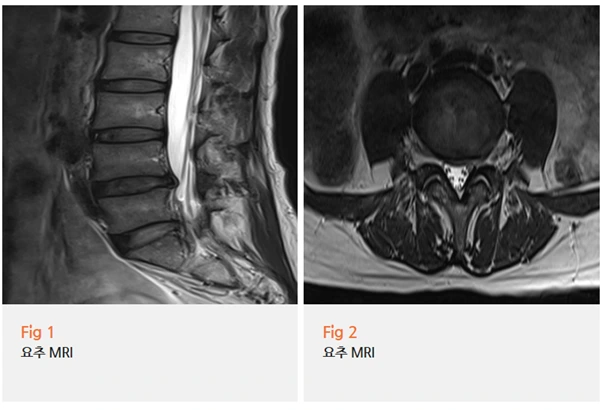

내원 당일 요추 MRI를 바로 시행했어요.

다리 저림 증상이 이 정도면 구조적 원인을 먼저 확인해야 했거든요.

결과를 보니… 네.

요추 추간판 탈출증, 쉽게 말하면 허리디스크 소견이 확인됐어요.

탈출된 디스크가 신경을 직접 누르고 있는 상태였고,

하지 근전도 검사에서도 만성 요추 신경근병증 소견이 함께 확인됐어요.

다리저림증상의 원인이 명확해지는 순간이었습니다.